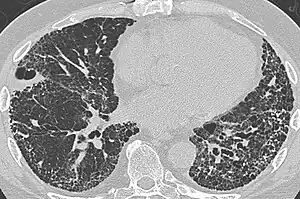

UIP may be diagnosed by a radiologist using computed tomography (CT) scan of the chest, or by a pathologist using tissue obtained by a lung biopsy.

Radiologically, the main feature required for a confident diagnosis of UIP is honeycomb change in the periphery and the lower portions (bases) of the lungs.[3]

On high-resolution computed tomography (HRCT), the following categories, depending on imaging findings, have been recommended by a collaborative effort by the American Thoracic Society, European Respiratory Society, Japanese Respiratory Society, and the Latin American Thoracic Society:[4]

- Probable UIP pattern:[4]

- Predominantly subpleural and basal

- Often heterogenous distribution

- Reticular pattern with peripheral traction bronchiectasis or bronchiolectasis

- There may be mild ground-glass opacity